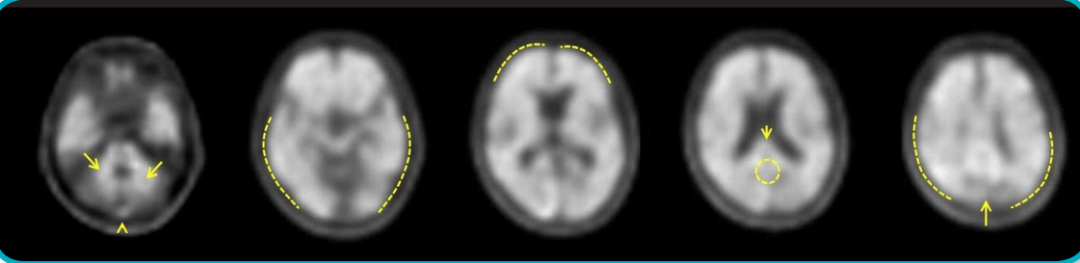

Neuraceq为一种脑β-淀粉样蛋白(Aβ)正电子发射断层扫描(PET)显像剂,是由德国Life Molecular Imaging (LMI)公司所研发,该显像剂通过PET/CT或PET/MRI设备进行PET成像,可对成年患者脑内β-淀粉样蛋白(Aβ)水平进行精准测定,以评估阿尔茨海默病(AD)导致认知功能下降的病因。

氟[18F]比他班注射液是一种18F标记的二苯乙烯衍生物,可与AD患者大脑皮层中的Aβ斑块特异性结合,不与组织中的Tau或α-突触核蛋白作用;氟[18F]比他班注射液通过18F核素产生正电子信号,由PET/CT或PET/MRI设备进行PET扫描,以PET图像检测大脑各区的Aβ斑块形成信号。